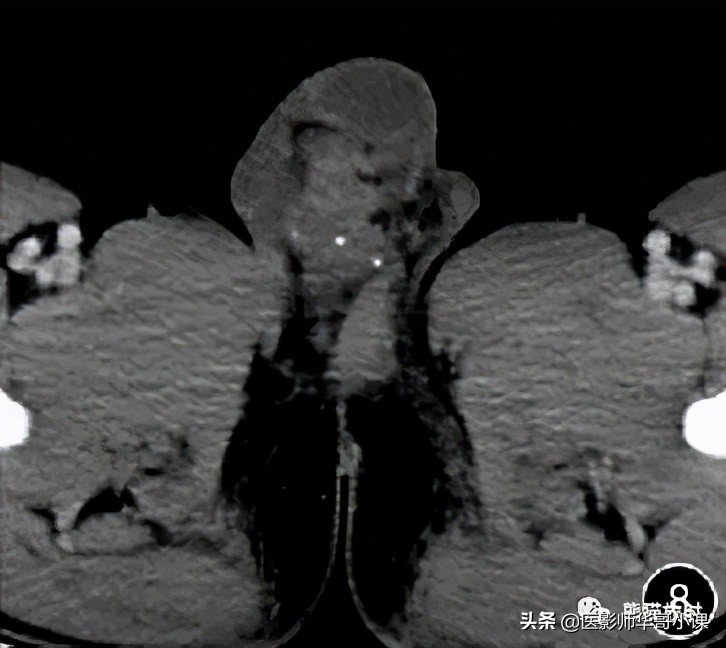

![[精品课件]畸胎瘤及精原细胞瘤(*丸睾**肿瘤及肿瘤样变CT及MR表现)](http://static.shicijianshang.com/origin/pgc-image/427c42f6a8de4cf6aa5a4a0792e59375.jpg)

图8 男,25岁, 右侧阴囊血管瘤 。右侧阴囊不规则软组织肿块,并多发小类圆形钙化灶,轻度强化。